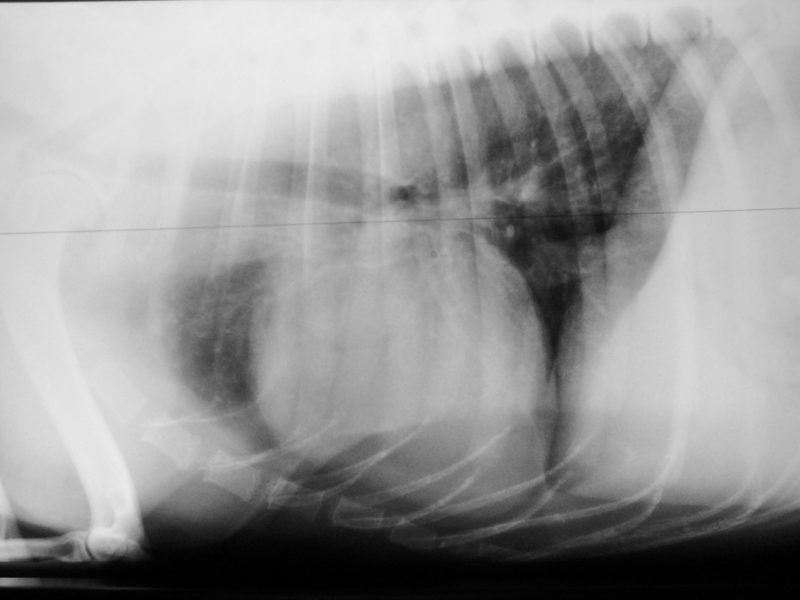

Der persistierende Ductus arteriosus botalli (PDA) bei Schäferhund Rike. In dem warmen Sommer 2018 ist die 7-jährige Schäferhund-Mischlingshündin  "Rike" mit Wärmelabilität und Kurzatmigkeit aufgefallen. Zum Herbst und Winter besserte sich die Symptomatik mit fallenden Temperaturen - anders als erwartet - jedoch nicht. Beim Haustierarzt wurde ein Herzgeräusch festgestellt und aus diesem Anlass ein Röntgenbild des Brustkorbs angefertigt. Der Befund bestätigte die Befürchtung: der Herzschatten war viel zu groß. Eine weiterführende Abklärung wurde empfohlen, und so kam die Hündin zur Vorstellung in meine Praxis für Tierkardiologie.

Rike wurde einer modernen Echokardiographieuntersuchung nach nationalem und internationalem Standard unterzogen und zusätzlich eine 3D/4D-Bildbetrachtung vorgenommen und ihre Herzmuskelleistung via Speckle Tracking untersucht. Die Untersuchung bestätigte eine offene Verbindung zwischen Aorta und Pulmonalrterie, die sich bei der Geburt hätte schließen müssen. Durch die Volumen und Drucküberladung kommt es zu einer Linksherzbelastung, die zu einer deutlichen Vergrößerung der linken Kammer geführt hat. Infolge der Kammervergrößerung wird die linke Vorkammer-Kammerklappe undicht und zunehmend Blut in Richtung Lunge zurücklassen, was das Stauungsrisiko weiter steigert. Typischerweise erhöht sich wie auch bei Rike der Aortendruck, ohne dass anatomische Anzeichen einer Stenose festzustellen wären. In der Pulmonalarterie ist im Farbdoppler ein chaotisch-turbulentes Signal zu sehen, während die Ductusampulle laminar bleibt. Im EKG zeigten sich bereits verlängerte Überleitungszeiten im Kammerkomplex QRS und Senkung des ST-Segmentes, als Zeichen einer Hypoxie des Herzmuskels.